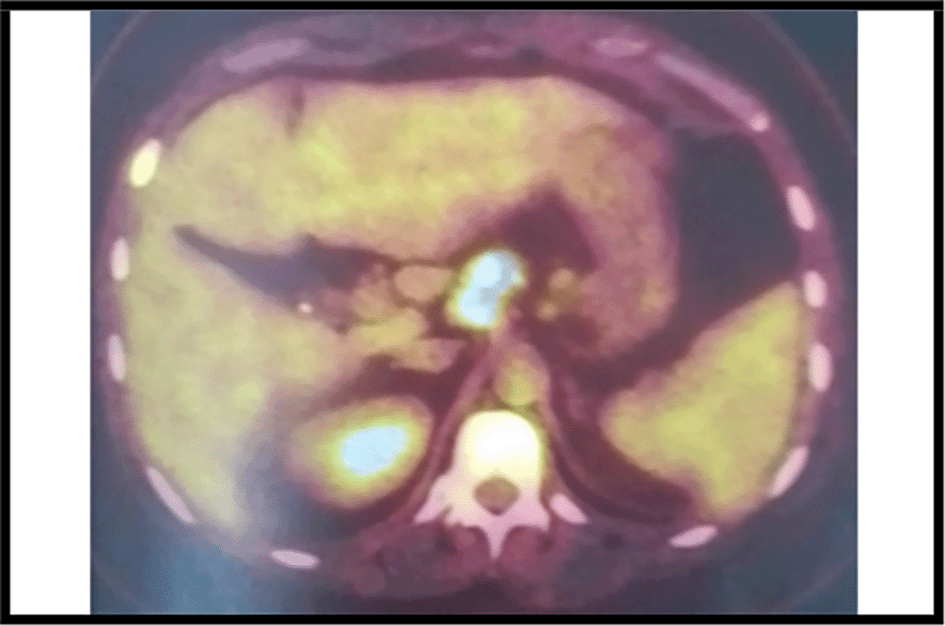

The 18-fluorodeoxyglucose-positron emission tomography (FDG-PET) showed many sites of activity of the disease, with a high metabolic fixation of the FDG in the lymph node stations (1L,3,5,6,7,8,9,10,11R) as well as subphrenic adenopathy. Besides, it revealed an intense endotracheal metabolic fixation (Figures 4, 5). Moreover, the bone marrow biopsy was negative.

It is worth mentioning that the PET scan is a reliable imaging tool for the diagnosis as well as for the staging of lymphoma especially in this case because mediastinal adenopathy may be due to infectious or inflammatory diseases.6,7 In our case, this exam showed an intense metabolic fixation FDG in many ganglionar areas as well as an endotracheobronchial fixation. It is also very interesting for the follow-up.